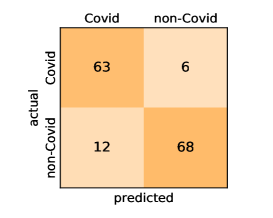

Here, we present and discuss the obtained results for detecting COVID-19 on the considered CT image datasets with different deep networks. We report the quantitative results along with the confusion matrices for every single architecture of the adopted networks.

On the SARS-CoV-2 CT dataset, ResNet101 achieves the best overall performance with respect to almost all evaluation metrics, with an average accuracy and F1-score of and , respectively. The model also achieves an average sensitivity rate of indicating that, on average, only two COVID-19 images are falsely predicted as negatives. It is also powerful enough to correctly identify all Non-COVID-19 cases with only one false positive resulting a specificity rate of . The highest sensitivity score of is achieved by the InceptionV3 model, where only one COVID-19 image is falsely predicted as negative on average. The SqueezeNet model obtains the lowest performance with respect to all evaluation metrics with a fairly acceptable average accuracy and sensitivity scores of and , respectively. Also the ShuffleNet architecture obtains satisfactory performance with approximately improvements on average for all metrics compared with SqueezeNet. Although the results obtained by these models are inferior compared with the rest of models, but they are more efficient. This matches their main objective of reducing the computational costs rather than improving their visual recognition abilities. The rest of models achieve competitive performance and very promising results with slight performance differences. Comparing the different variants of ResNet and DenseNet, we can see that the deeper variants from each architecture yield a slightly better performance. The deeper ResNet101 and ResNeXt101 show a marginal gain in performance compared with their shallower counterparts. The details about class-wise results for each model are summarized in the confusion matrices in Figure 9.